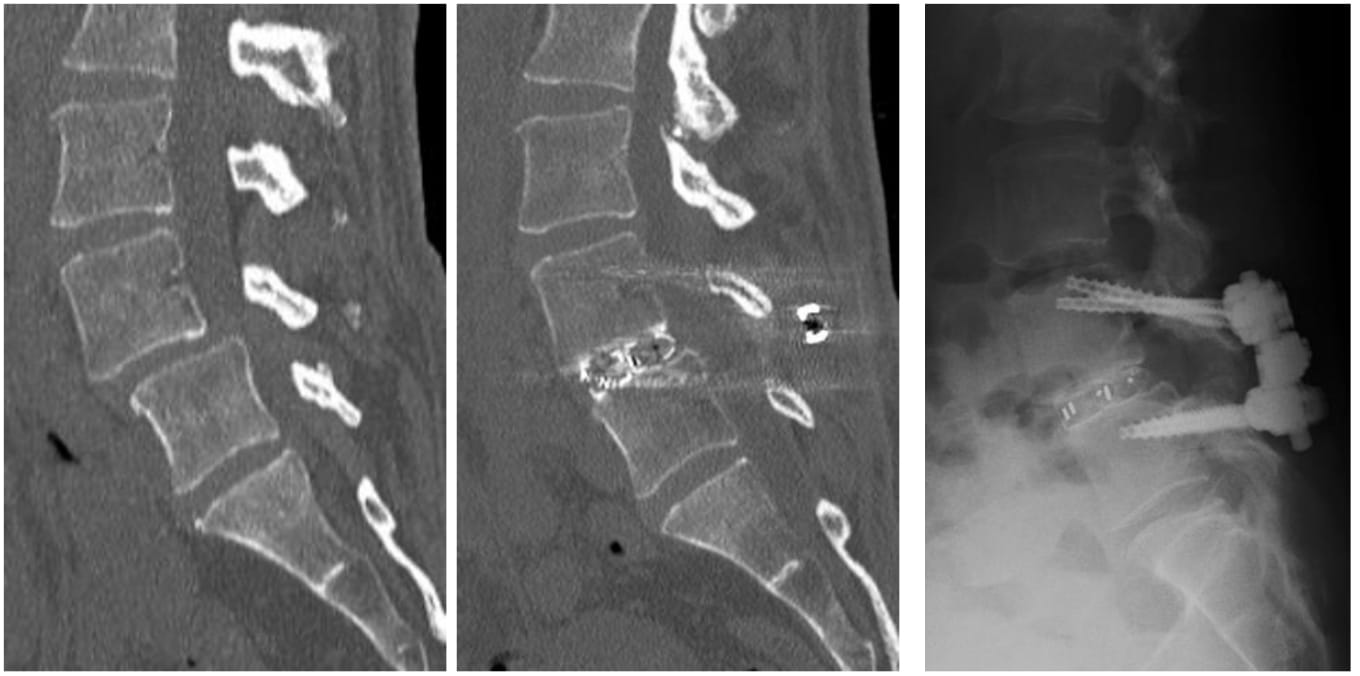

腰椎すべり症(背ぼねが前後にずれる病気)などの、脊椎がグラグラして痛みを生じている場合は、脊椎を安定化させるためにチタン・インプラントによる脊椎固定術が有効です。従来は大きく切開してインプラントを入れる手術が主流でしたが、近年では小切開で手術を行うことが出来るようになりました。椎弓根スクリュー(背ぼねを固定するネジのようなインプラント)を入れる際にも、経皮的スクリュー法(PPS法)や皮質骨経路スクリュー法(CBT法)という方法で、出来るだけ小切開で行うようにしています。

図3-1.MIST法による腰椎固定術の例

図3-2.腰椎すべり症に対する固定術の例 出来るだけ小切開で行うようにしています